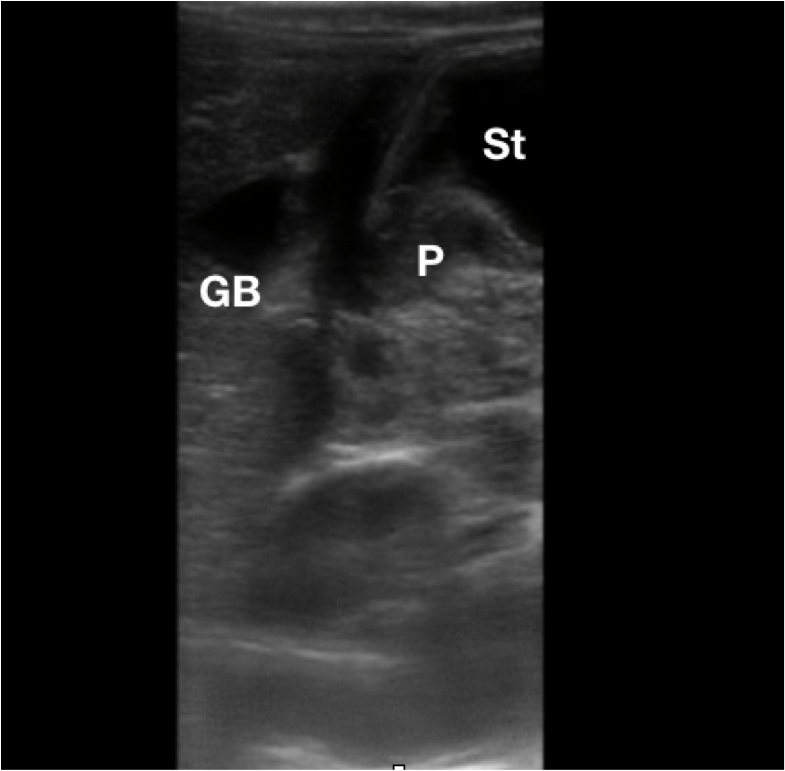

Figure 1. Anatomy of the stomach and pylorus (D: Duodenum, GB: Gallbladder, P: Pylorus, S: Body of Stomach)

- Pylorus is at the distal end of the stomach.

- Generally lies medial to the gallbladder.

- Anterior and lateral to the aorta and superior mesenteric artery.

- Figure 2. Sonographic anatomy of the pylorus (P) in relation to the gallbladder (GB) and stomach (St)